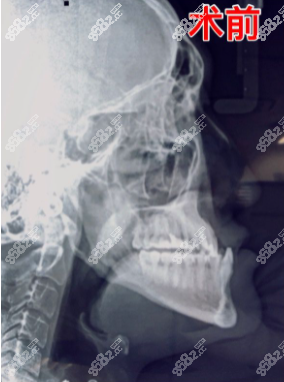

這是醫(yī)生給我拍的術(shù)前CT照片,說句不好聽的,真覺得自己像鞋拔子臉。

1. 遺傳性骨性地包天

2. 上頜發(fā)育不足,下頜發(fā)育過度

3. 下牙包上牙+偏頜

4. 鼻基底凹陷